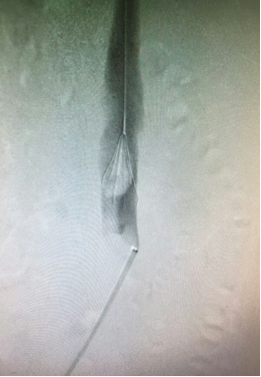

图为:入院立位腹部平片

图为:入院后再次尝试腔内回收滤器,经4h努力以失败告终